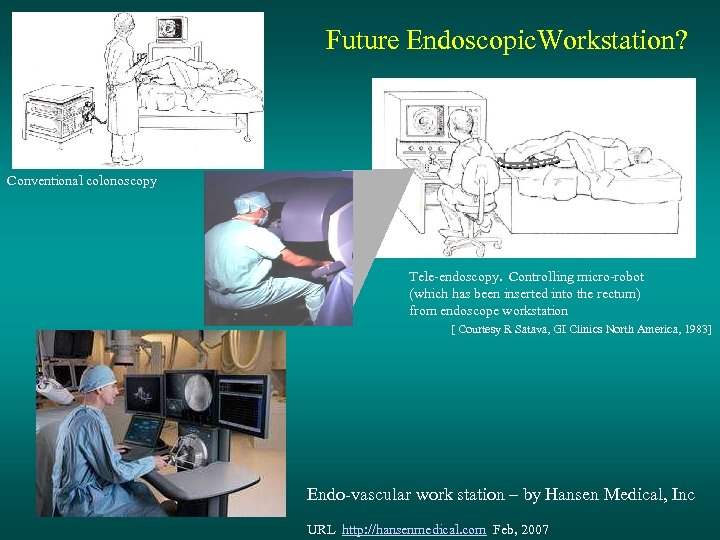

Future Endoscopic. Workstation? Conventional colonoscopy Tele-endoscopy. Controlling micro-robot (which has been inserted into the rectum) from endoscope workstation [ Courtesy R Satava, GI Clinics North America, 1983] Endo-vascular work station – by Hansen Medical, Inc URL http: //hansenmedical. com Feb, 2007

Future Endoscopic. Workstation? Conventional colonoscopy Tele-endoscopy. Controlling micro-robot (which has been inserted into the rectum) from endoscope workstation [ Courtesy R Satava, GI Clinics North America, 1983] Endo-vascular work station – by Hansen Medical, Inc URL http: //hansenmedical. com Feb, 2007